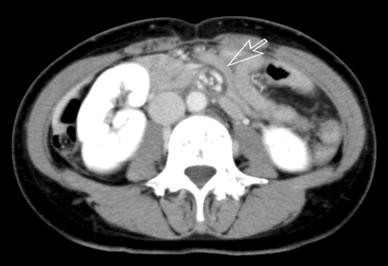

Early phase of enhanced computed tomography (CT) scan shows swirled appearance and twisting of the mesenteric artery (arrow, whirl sign) in a patient 443 days after laparoscopy-assisted distal gastrectomy (LADG)